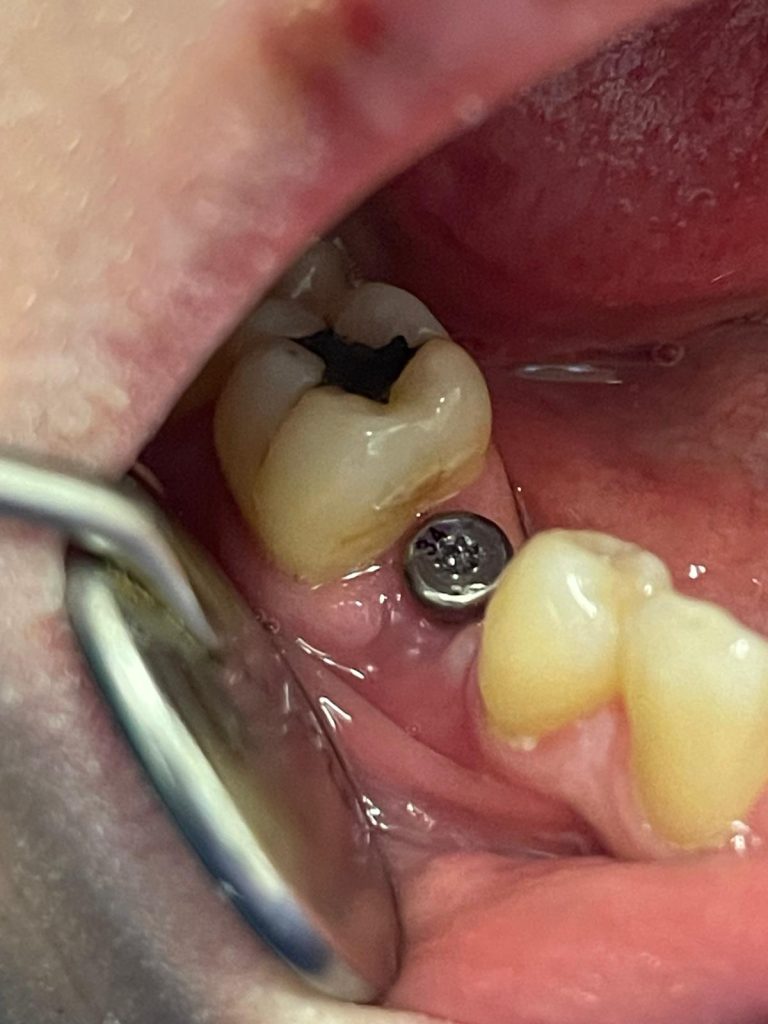

Osteointegrazione e tempi di guarigione

L’osteointegrazione richiede generalmente da 2 a 6 mesi, a seconda della zona trattata e delle condizioni individuali del paziente. Durante questo periodo l’impianto si stabilizza e diventa una base solida per il dente definitivo.

Applicazione della protesi definitiva

Una volta completata la guarigione, sull’impianto viene fissata la corona dentale definitiva, progettata per integrarsi armoniosamente con i denti naturali per forma, colore e funzione.